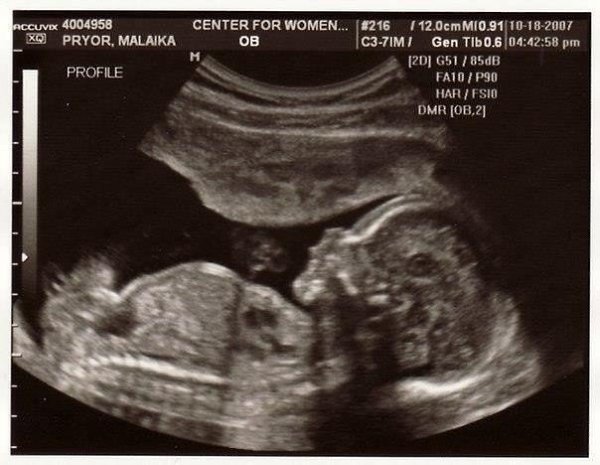

Девочки, счастье это не затяжка сигареты и глоток пива, счастье - это когда ты приходишь к врачу и тебе говорят, "Ваш малыш развивается хорошо, отклонений нет!"